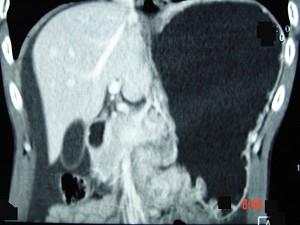

问题 男,65岁,中上腹痛腹胀、消瘦、乏力、纳差,影像检查如图,最可能的诊断是 ( )

选项 A、胃窦癌 B、胃淋巴瘤 C、萎缩性胃炎 D、肥厚性胃炎 E、胃间质瘤

答案 A